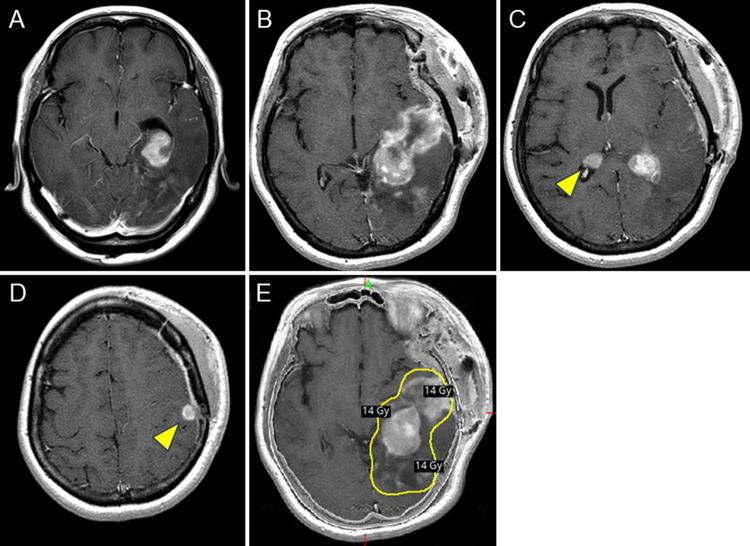

A 56-year-old woman underwent partial tumor removal for PCNSL in the left temporo-occipital lobe at another hospital. One and a half months later, a new lesion was observed, and she underwent GKRS, including the residual lesion. She was treated with multiple chemotherapy regimens including R-MPV (rituximab, methotrexate, procarbazine, vincristine) but relapsed repeatedly and was administered tirabrutinib. Four years after GKRS, the gadolinium-enhanced lesion slowly grew. Tumor recurrence or radiation necrosis was suspected, and surgical removal was performed. The tissue was composed of nonmalignant brain tissue and fibrinized hematoma, which demonstrated strong expression of VEGFR-1 on immunostaining, and the pathological diagnosis was CEH.

一名56岁女性在另一家医院接受了左颞枕叶PCNSL部分肿瘤切除术。一个半月后,发现一个新病灶,她接受了包括残留病灶在内的GKRS治疗。她接受了多种化疗方案,包括R-MPV(利妥昔单抗、甲氨蝶呤、丙卡巴肼、长春新碱),但多次复发,并接受了替拉鲁替尼治疗。GKRS治疗四年后,钆增强病灶缓慢增大。怀疑为肿瘤复发或放射性坏死,遂进行手术切除。组织由非恶性脑组织和纤维蛋白化血肿组成,免疫染色显示VEGFR-1表达强烈,病理诊断为CEH。